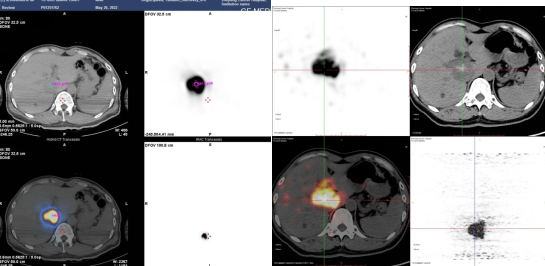

图7.90钇(90Y)放射性微球治疗肝转移瘤